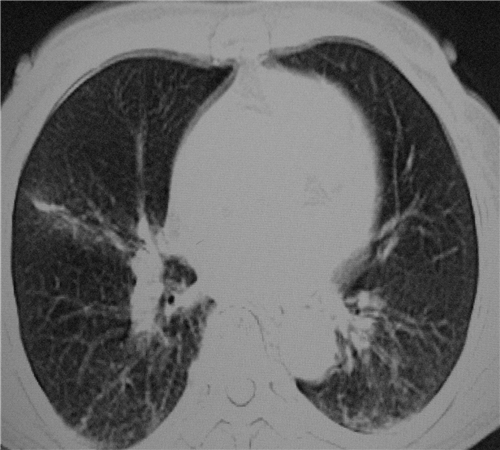

标题: CT26849:女67岁反复胸痛两天余,临床考虑夹层。 [打印本页]

标题: CT26849:女67岁反复胸痛两天余,临床考虑夹层。

右肺感染,未见夹层。

既然考虑夹层,建议强化!另:右下肺感染!

1)右肺感染性病变。2)建议行ct增强扫描或mri检查排除主动脉夹层。

双下肺感染,右侧显著。有无夹层,增强扫描后再诊断。

1. 感染性病变,2.未见夹层,3.食道未见异常。